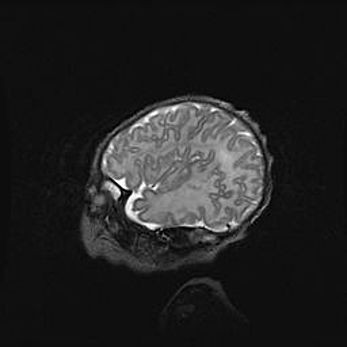

Открытая гидроцефалия.

Возраст: 6 месяцев 15 дней

Вес: 6200 г

Пол: женский

Окружность головы: 41 см

Срок гестации: 38 недель

Гидроцефалия головного мозга у новорожденных – это скопление избыточного количества цереброспинальной жидкости в головном мозге. Ее избыточное скопление в мозге приводит к патологическому расширению желудочков мозга (четырех полостей, расположенных в глубине белого вещества мозга, заполненных цереброспинальной жидкостью и связанных узкими проходами).

Открытый тип гидроцефалии (сообщающаяся) наблюдается тогда, когда нарушен механизм всасывания ликвора в системный кровоток. При этом типе причиной заболевания чаще всего является перенесенные ранее инфекции (например: менингит),  либо же наличие крови в субарахноидальном пространстве.